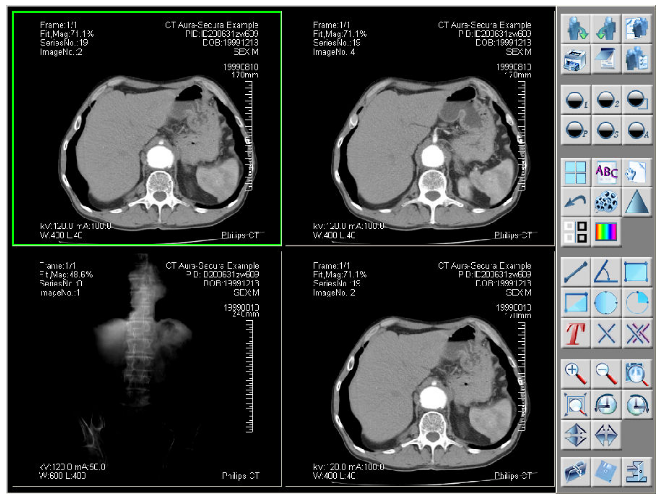

迅影PACS的影像增强技术

通常,从放射设备采集的原始图像动态范围很大,在显示设备上显示时进行的动态范围压缩大都是线性的,使得图像的细节往往不能满足放射医师的诊断需求,而一些非线性变换如伽马校正、直方图均衡化等也不能根本上改善图像的细节,传统的影像增强技术在改善图像边缘的同时,也增强了噪声。比较先进的处理办法是频域处理或多分辨率分析,其思路是把图像分解成不同分辨率的子图像,根据需要对这些子图像进行处理,包括增强和抑噪,重建以后可以得到较好的图像质量,在临床诊断上有很重要的应用价值。

注:传统的影像处理技术很难达到这种效果

局部处理(CR):

原始图像经普通边缘增强后的效果

通过多尺度对比度增强技术可成功应用在PACS系统针对X-ray图像的处理过程中。图像中不同尺寸的低对比度细节的视觉质量显著改善,这种处理方式不会产生严重的边界效应(振铃效应),这一优点使得此技术能够广泛应用于CT、MR、DR、CR、数字乳腺诊断等成像。